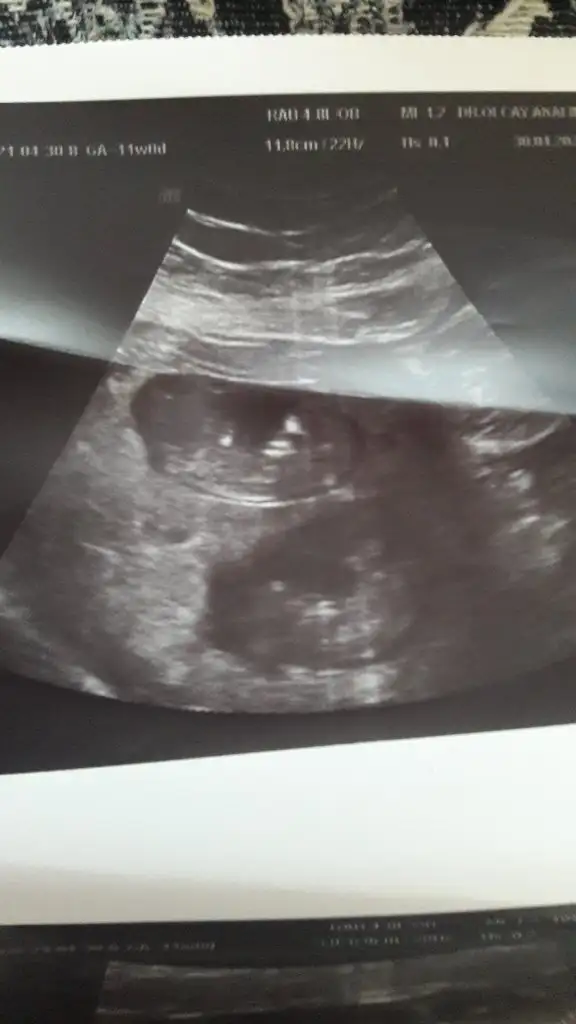

14+3 tahminde bulunurmusunuz🤦‍♂️

• USER_SCOPED_TEMP_DATA_MSGR_PHOTO_FOR_UPLOAD_1619699207153_6793510863365994738.webp

USER_SCOPED_TEMP_DATA_MSGR_PHOTO_FOR_UPLOAD_1619699207153_6793510863365994738.webp

24,1 KB · Görüntüleme: 67